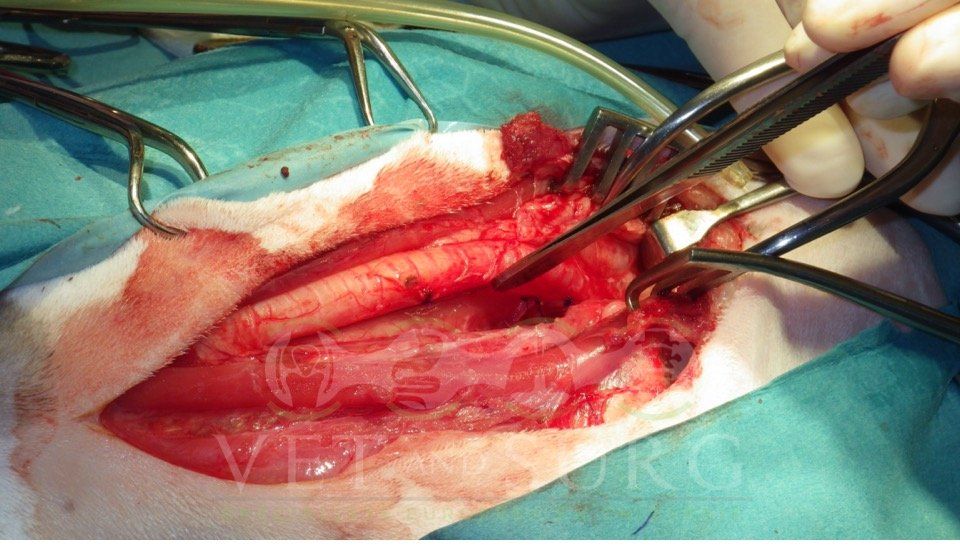

Dans la gestion des pathologies respiratoires, cardio-vasculaires, et des atteintes médiastinales et diaphragmatiques.